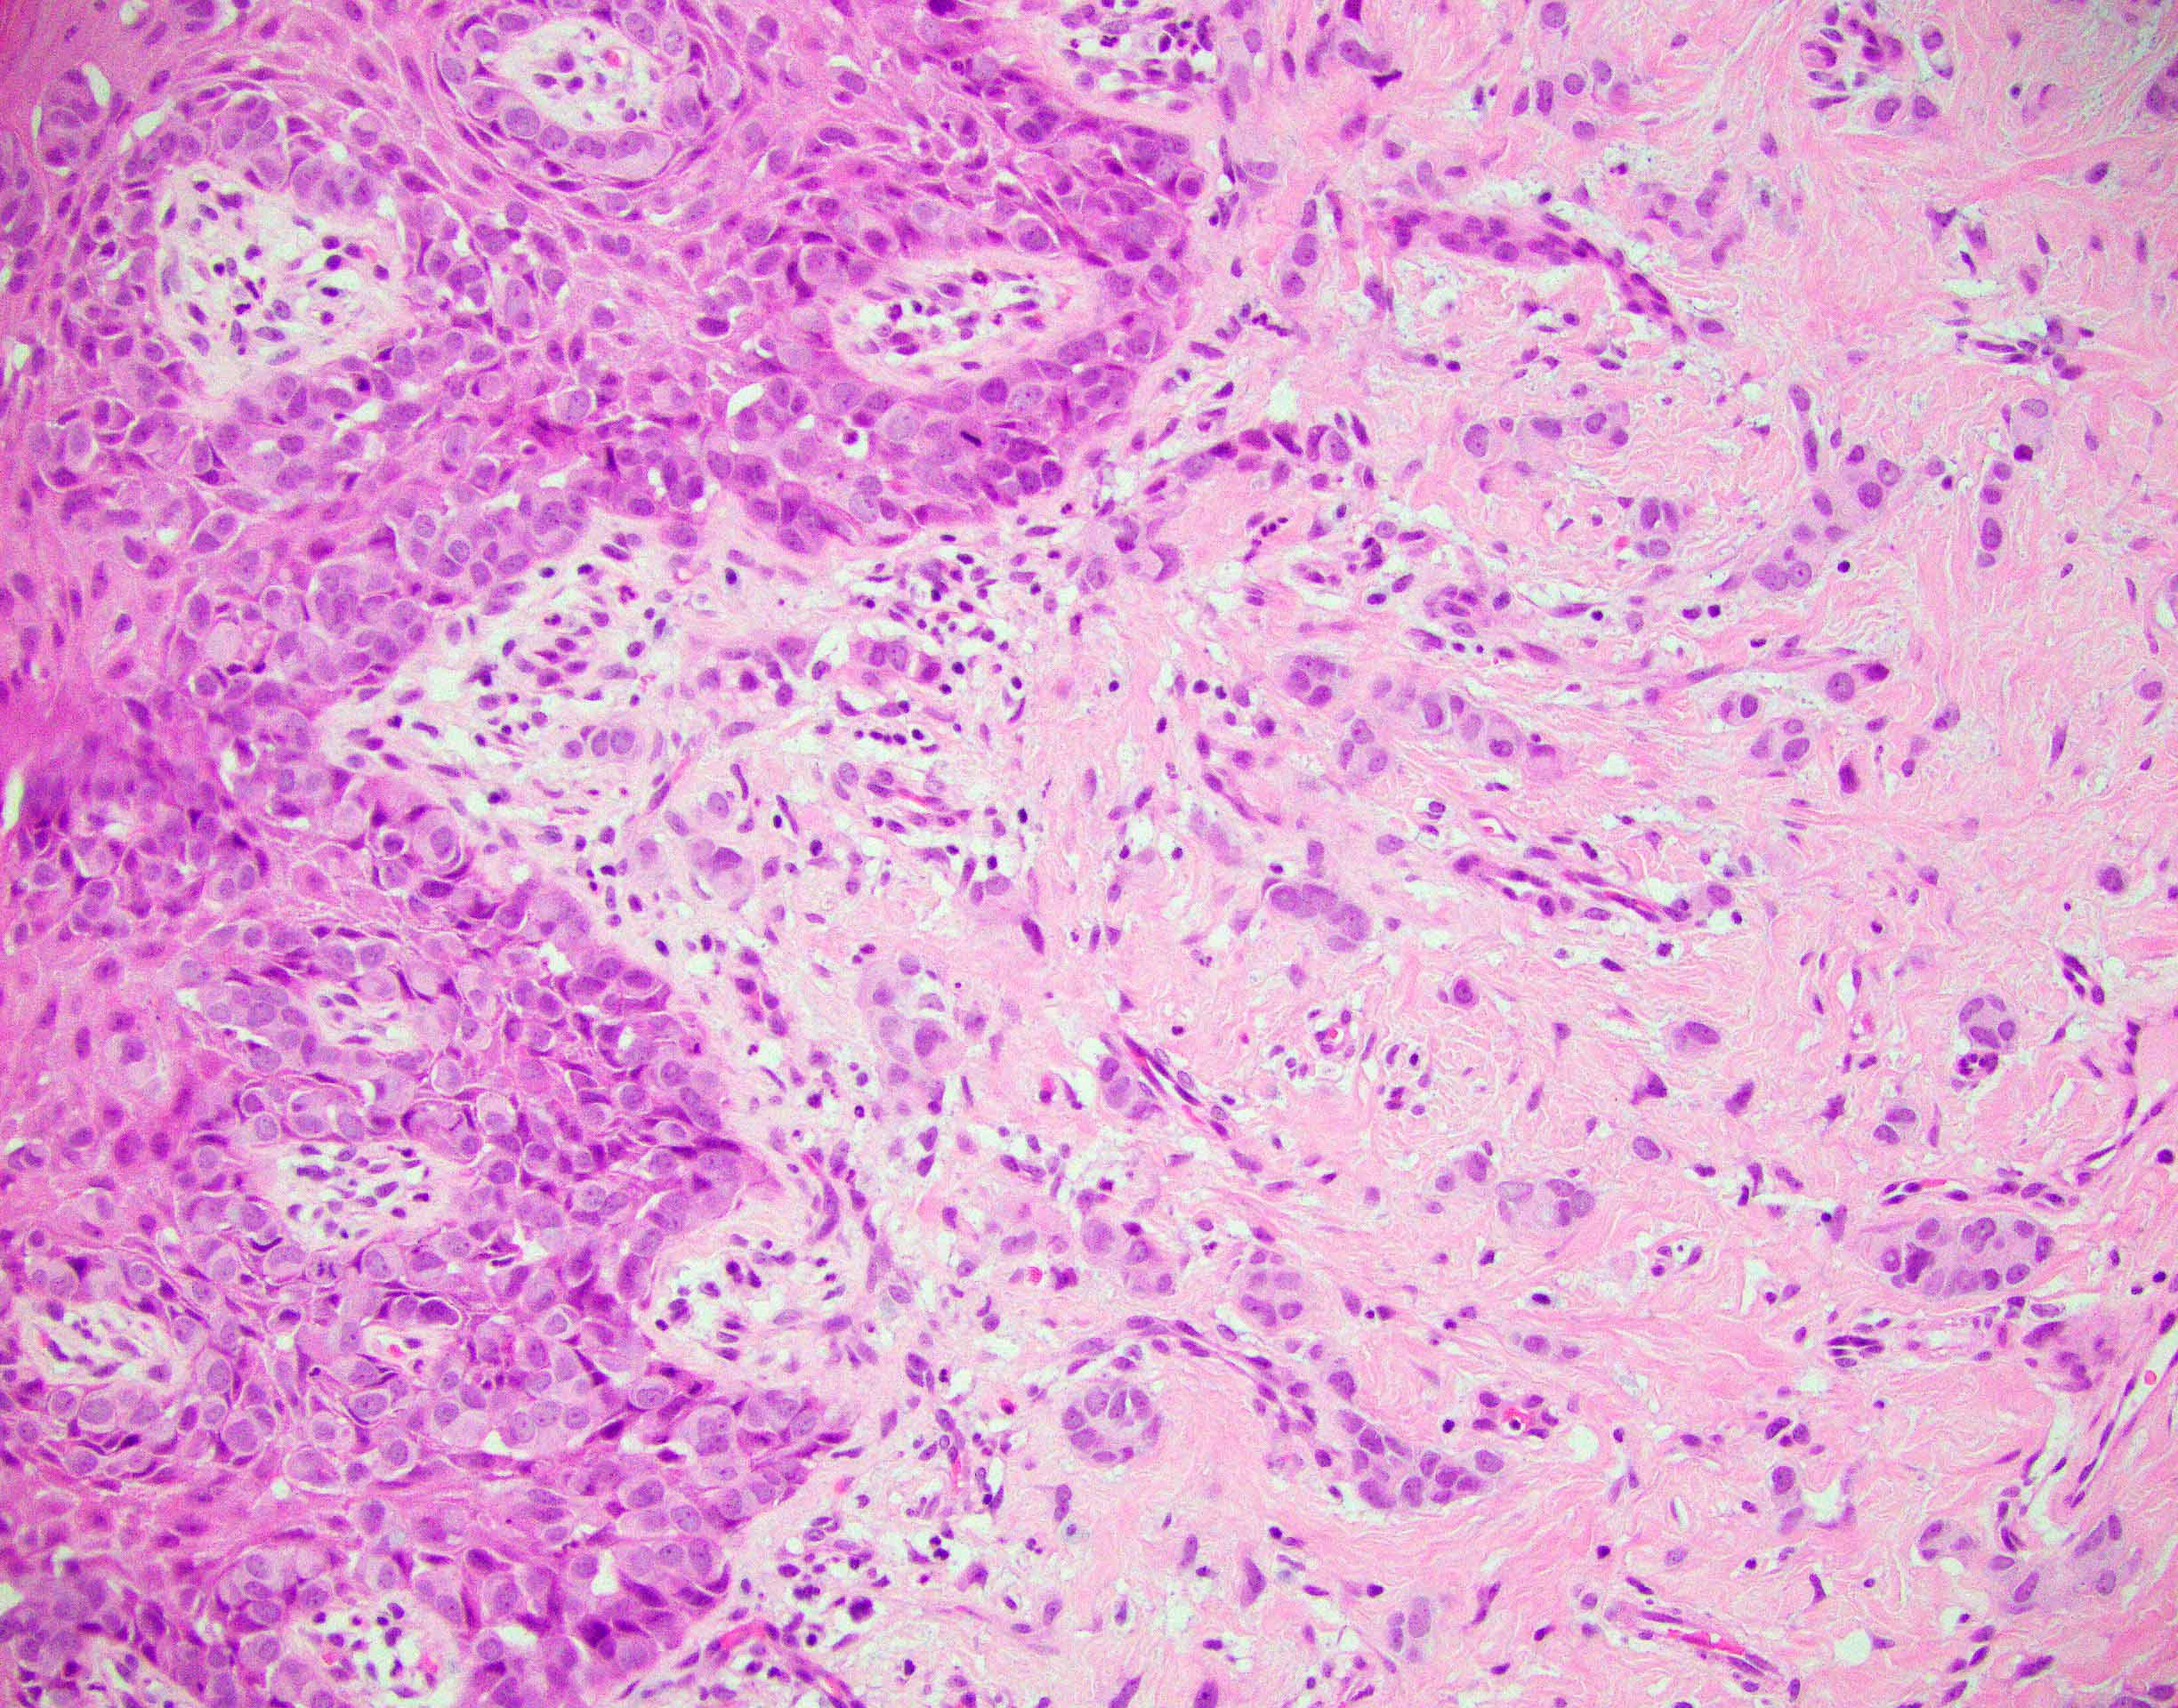

Microscopic (histologic) description

- Paget cells are enlarged polygonal epithelial cells with abundant pale cytoplasm, large nuclei and small to prominent nucleoli

- Intracytoplasmic mucin is frequently present

- Rarely, gland formation may be seen

- Prominent host inflammatory response in the superficial dermis is frequently seen

- Dermal invasion

- Single cells or small groups of cells infiltrating the dermis with an associated desmoplastic reaction

- Groups of cells may form glandular structures

- May be associated with dense dermal inflammatory response

Microscopic (histologic) images

Contributed by Priya Nagarajan, M.D., Ph.D. and Lucy Ma, M.D.